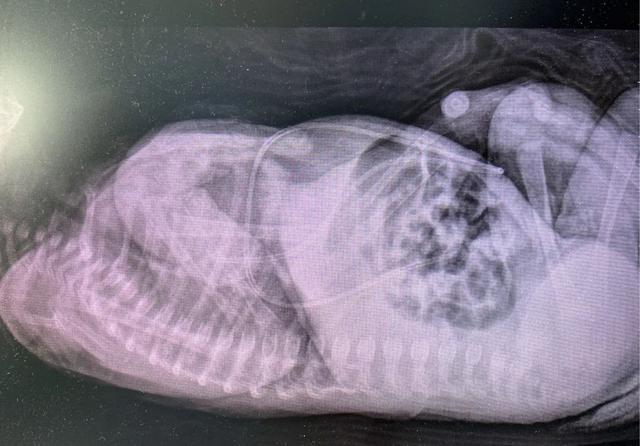

►床旁X光片确认导管尖端位置